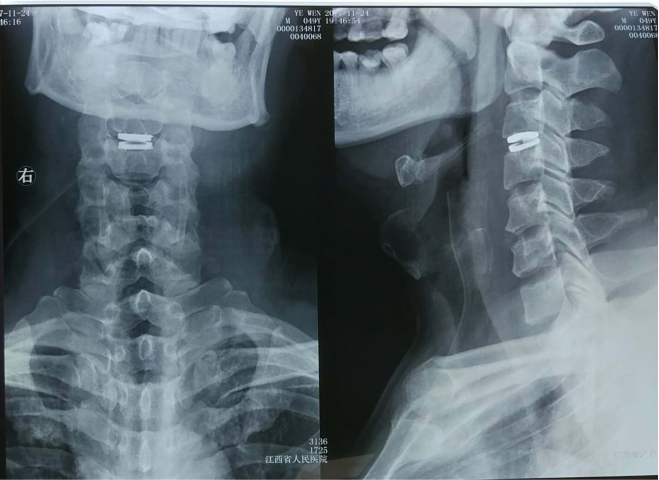

国内首例新型人工颈椎间盘置换手术在江西省人民医院成功完成

2017-11-27 10:33:13